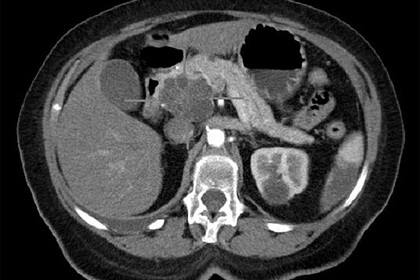

Кроме того, в последнее время появились новые методы ранней диагностики и лечения рака поджелудочной железы. С помощью МРТ можно идентифицировать заполненные жидкостью кисты внутри органа, которые повышают вероятность развития опухоли. Также можно взять образцы пищеварительного сока, выделяемого железой, или стула, чтобы выявить маркеры раннего рака.